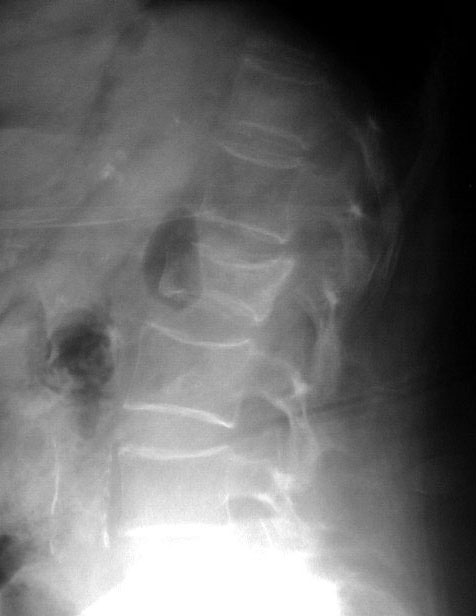

SIGNO DE LA C

Signo de coalición subtalar (fusión calcáneo-astragalina) en la radiografía lateral del tobillo. La «C» se forma por el límite medial de la cúpula talar y el límite posteroinferior del sustentaculum tali.

En la radiografía lateral de tobillo hemos marcado con flechas la «C» que da nombre al signo.

La fusión calcáneo-astragalina (flecha) se comprueba en el corte coronal de TC de tobillo.